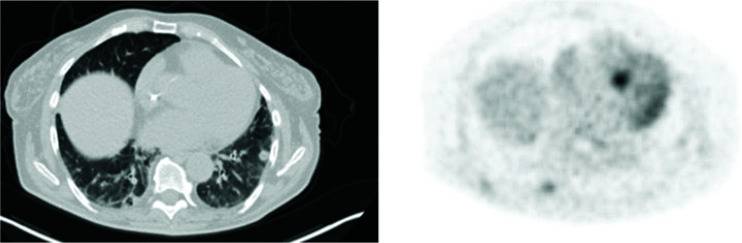

Immunotherapy has revolutionized the treatment landscape for solid tumours. Here, we describe the case of a 69-year-old woman with advanced endometrial cancer (EC) who achieved prolonged disease control with immunotherapy. The patient was diagnosed with stage IIIC EC in February 2020 and was treated with carboplatin and paclitaxel, followed by radiotherapy. Relapses occurred in February 2021 (treated with doxorubicin and palliative radiotherapy) and July 2022 (treated with a carboplatin rechallenge). Pembrolizumab and lenvatinib were started in November 2022. Although the initial scan showed progressive disease, restaging 2 months later showed stable disease, which was maintained on pembrolizumab and lenvatinib until progression in October 2024. This article is part of the New treatment options for advanced endometrial carcinoma Special Issue: https://www.drugsincontext.com/special_issues/new-treatment-options-for-advanced-endometrial-carcinoma.

Abstract Image